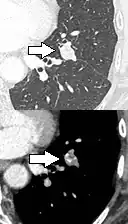

Thin slice and maximal intensity projection of a lung nodule, the latter better visualizing vascular convergence.[9]

• Vascular convergence is where vessels converge to a nodule without adjoining or contacting the edge of the nodule, and is mainly seen in peripheral subsolid lung cancers.[9] It reflects angiogenesis.[9]